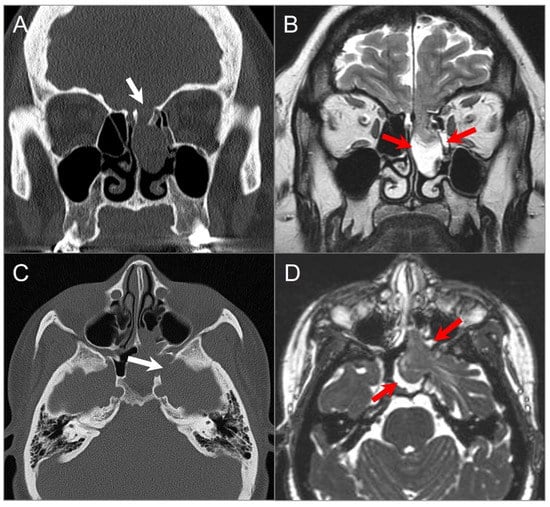

5.6. Invasive Fungal Sinusitis

4.1.5. Extension of Head and Neck Malignancy